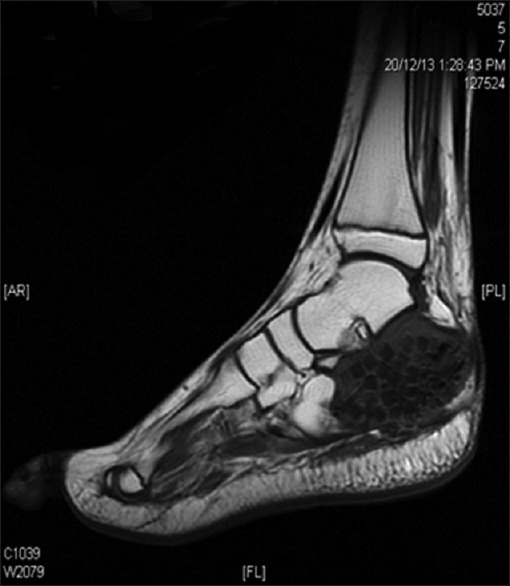

Radiograph of the left heel showed an expansile lytic lesion in the calcaneum with cortical break and no periosteal reaction [Figure 1]. Magnetic resonance imaging (MRI) of the ankle revealed well-defined expansile cystic lesion in the calcaneum. The lesion appears predominantly isointense on T1-weighted imaging and heterogeneously hyperintense in T2-weighted imaging with septations and fluid layering [Figure 2]. There is a breach in the medial aspect with the extension of the lesion into the adjacent soft tissue with enhancement on postcontrast study. The radiologic impression was of aneurysmal bone cyst.

| Figure 2:On T1-weighted imaging, the lesion was seen as low intensity with bone grafts